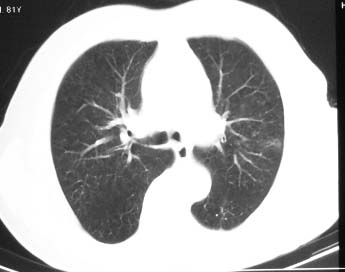

81 男 以头昏入院

两肺多发异常密度,其中双上肺病变主要为纤维增殖性改变;右中肺内侧段病变密度相对均匀,无恶性特征,周围可见卫星灶和浸润表现,邻近胸膜稍增厚,所见纵隔层面无肿大淋巴结和胸腔积液。提示结核性改变。如果可能建议强化。

右肺中叶团片影,似多病灶融合而成,密度不均匀,边界清楚,周围见明显的索条及小结节,左肺亦见斑片影,纵隔窗未见肿大淋巴结.多考虑:肺内慢性炎性病变伴纤维化.

右肺上叶肿块,其远侧段肺组织炎性渗出性改变,局部胸膜粘连,肺门侧边缘光滑锐利,可见结节样病灶;右肺尖纤维索条状影,局部肺纹理纠集,纵隔窗窗宽不合适,病灶内部情况显示不清,未见明显淋巴结肿大及钙化.

考虑:1.右肺上叶周围性肺癌并肺内转移;2.右肺尖陈旧性结核.3.左肺炎性病灶.

两肺多发异常密度,其中双上肺病变主要为纤维增殖性改变;右中肺内侧段病变密度相对均匀,无恶性特征,周围可见卫星灶和浸润表现,邻近胸膜稍增厚,所见纵隔层面无肿大淋巴结和胸腔积液。提示结核性改变.

符合多叶多段多形态的特点.

右肺中叶软组织块,其周围可见多个类圆形结节,右肺上叶尖段见斑片、索条状致影,左肺小结节,见分叶、毛刺及胸膜凹陷征。1.左肺周围型肺癌伴右肺内转移; 2.右肺上叶陈旧性结核。

老年人,适用多元论,考虑 :1、左肺周围型肺癌伴右肺内转移; 2、右肺上叶陈旧性结核。